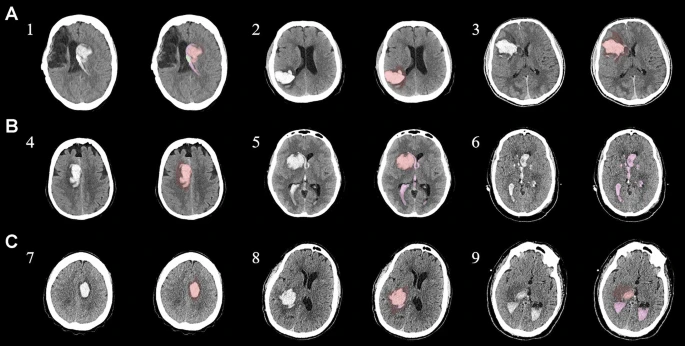

圖1:每個(gè)間充質(zhì)干細胞治療患者按組的原始非對比計算機斷層掃描和分割結果

本研究納入2018年1月1日至2020年10月31日發(fā)病168小時(shí)內發(fā)生急性ICH的患者。間充質(zhì)干細胞被靜脈注射給9名患者(5名女性,4名男性),平均年齡(范圍)為61(36-84)歲。表1總結了人口統計學(xué)和臨床??特征 。出于描述目的,患者按照入組順序獲得編號,并連續分配到三組中的一組,每組三人。根據模型 2 分割,ICH體積范圍為0.1至54.9mL(平均ICH體積為23.5mL)。5例ICH累及局部腦葉,其余則位于基底節或外囊深處。在三名患者中,ICH位于丘腦(圖1),在一名患者中,血腫位于多個(gè)腦結構(即尾狀核、殼核和蒼白球)。平均而言,MSC在ICH后3天進(jìn)行注射。